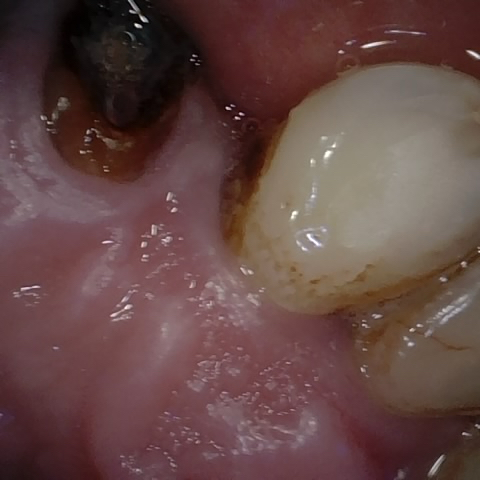

Annotated as "Good"